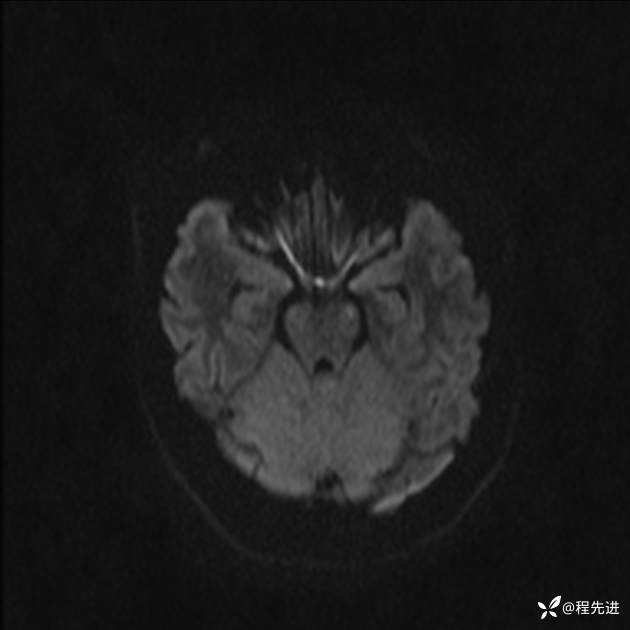

【患者信息】:女,25岁

【现病史及既往史】:言语含糊、意识状态改变1天。有下段剖宫产术10天病史。